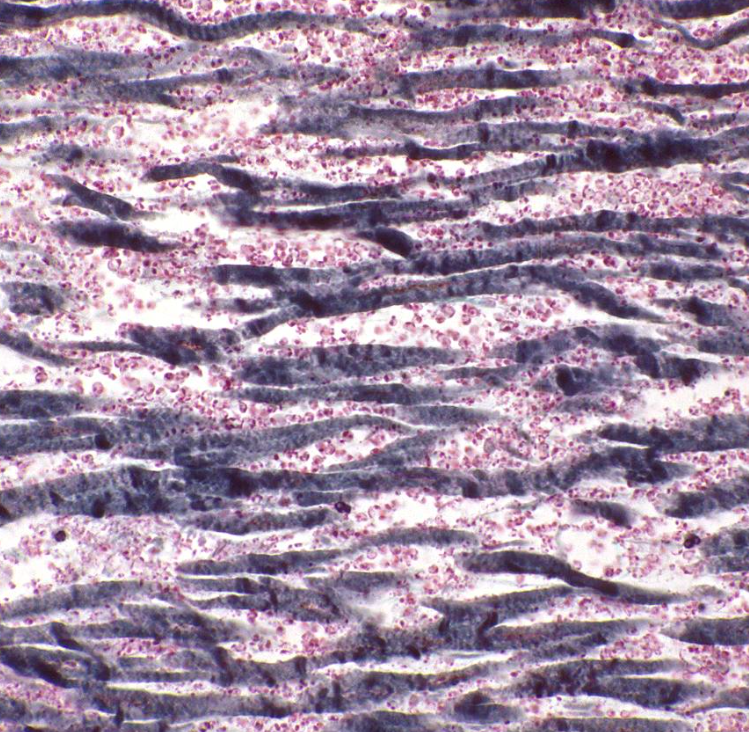

When would this histopatholigcal slide from an MI likely to have occurred

Less than 1 day coagulative necrosis

Less than 7 days

1-3 week

3-6 weeks